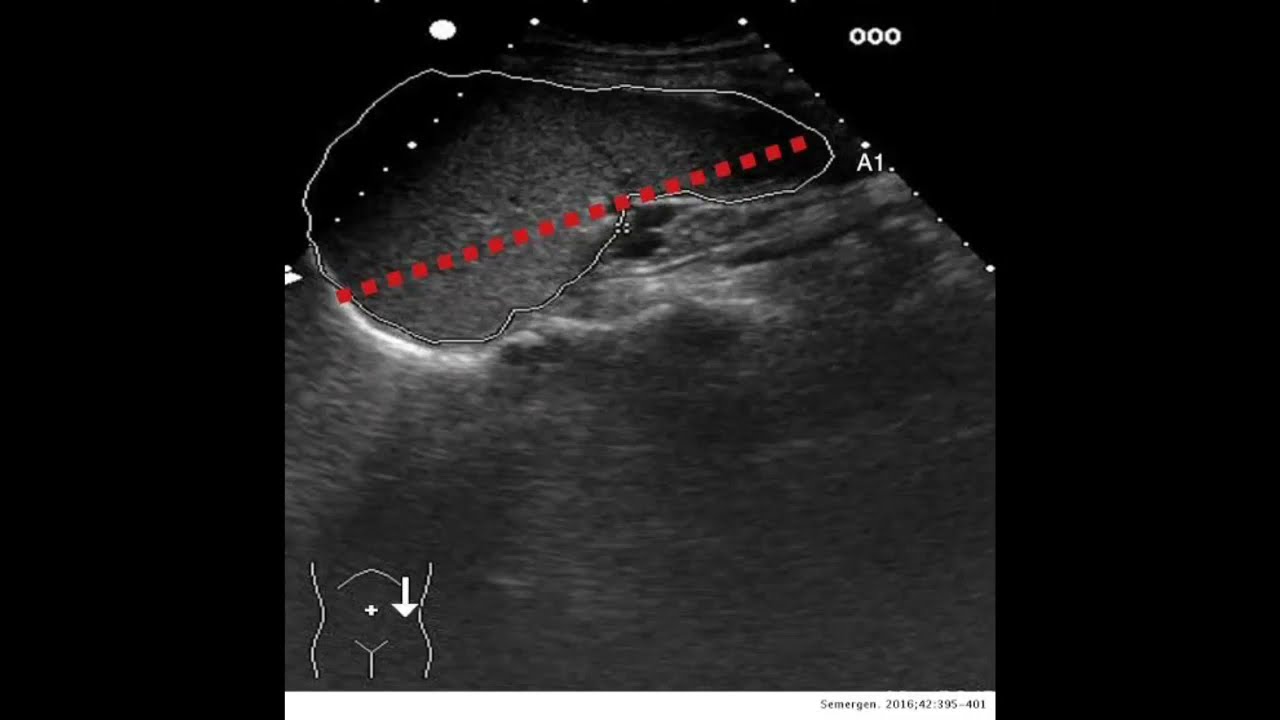

Webmedidas del bazo en ecografía. von | Nov 9, 2021 | la importancia de los peces en el medio ambiente | empresas mexicanas en portugal | Nov 9, 2021 | la importancia de los peces. WebEl Bazo es un órgano difícil de estudiar, cuando uno comienza a formarse en ecografía cuesta mucho ubicarlo, capturarlo, aunque sepamos su localización.Pero. WebInicio Manuales de ecografia Ecografía clínica básica Bazo. Bazo. diciembre 14, 2012. Facebook. Twitter. Pinterest. WhatsApp. Linkedin. Este contenido. WebMedidas normales del hígado a nivel de la línea medio clavicular según la talla* (en cm: +/- 2 DE.) *Siegel Marylin. Ecografía pediátrica. Ed. Marban. 2004 Dimensiones del bazo. WebLas mujeres presentaron una edad de 36,37±10,83 años, altura de 164,22±4,72 cm, peso de 60,26±7,11 kg, IMC de 22,30±2,09 kg/m2, AB de 7,58±1,56 cm, LB de 9,87±1,28 cm,. WebEn una radiografía del abdomen realizada por otros motivos también se puede observar el aumento del tamaño del bazo. Por lo general es necesario recurrir a una ecografía. WebUtilidad y fiabilidad de la ecografía clínica abdominal en medicina familiar (2): grandes vasos, bazo, nefrourológica y ginecológica

Técnica ecográfica para valoración del bazo.

Nuevo Ecografía de bazo y retroperitoneo | Medicina de Familia. SEMERGEN popular

Veamos Ecografía de bazo y retroperitoneo | Medicina de Familia. SEMERGEN Nuevo